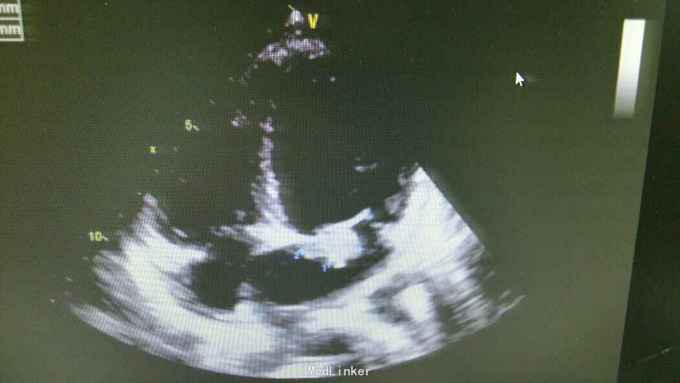

查体:T37.0℃,P110次/分,R26次/分,BP96/68mmHg。发育正常,营养一般,神志清楚,对答切题,轮椅送入院,查体合作。全身皮肤粘膜无黄染、皮疹,出血点及淤斑,未见Janeway结节,未见Osler结节及甲床下出血,无发绀,未见杵状指、趾,周围血管征阴性。浅表淋巴结未及肿大。巩膜无黄染,结膜无出血。口腔黏膜光滑,咽不红,扁桃体部大,颈静脉无明显搏动,未见怒张,气管居中,胸背部听诊双下肺闻及细小湿啰音。心前区无隆起或抬举性搏动,心尖搏动以左侧第六肋间锁骨中线外1.5cm处明显,未扪及震颤,心界向两侧稍扩大,心率110次/分,律齐,心音有力,P2稍亢进,无固定分裂,心尖区闻及3-4/6级收缩期吹风样杂音,向心底部传导,未闻及舒张期杂音,未闻及心包摩擦音。腹平软,无压痛及反跳痛,肝脾肋下未及,肠鸣音正常。脊柱、四肢关节无异常,活动好,双下肢无浮肿。 2015年10月30日汕头市中心医院心彩超:二尖瓣及瓣下腱索及左室心内膜多发赘生物形成,二尖瓣前瓣穿孔,重度二尖瓣关闭不全,左心系统扩大,心肌舒张功能下降,收缩功能正常,感染性细菌性心内膜炎,微量心包积液。 2015-11-1血常规:中性粒细胞比例 0.949,血红蛋白浓度 117.000(g/L),中性粒细胞计数 18.360(10E9/L),白细胞计数 19.350(10E9/L),血小板计数 343.000(10E9/L),红细胞计数 4.350(10E12/L)。 B超:双侧颈动脉血流通畅,双侧椎动脉未见狭窄。双侧甲状腺不大、未见占位,血供尚丰富。双侧颈部淋巴结声像,双侧乳腺未见明显占位,超声BI-RADS分类1类,双侧腋窝淋巴结声像。双肾未见结石与积水,双肾动脉主干血流连续,膀胱未见明显结石,双侧肾上腺区未见明显占位。肝脾胰不大,未见占位,胆囊未见明显结石,子宫及双侧附件区未见明显占位,宫后积液(少量)。 胸部CT:1、两下肺叶后基底段局部节段性肺炎。右肺中叶少许纤维化病灶。2、双侧胸腔少量积液。 胸片:考虑双肺炎症。 心电图:心率84次/分,窦性心律,肢体导联低电压,前间壁R波上升不良。 心彩超:1、考虑感染性心内膜炎:二尖瓣赘生物形成,伴中重度二尖瓣反流。中度三尖瓣反流。3、左房内径增大,肺动脉增宽。 头颅MR:左侧额叶、左侧放射冠侧脑室前角旁脑白质异常信号,考虑感染性病变及缺血灶可能性大。 2015-11-2查血常规:中性粒细胞比例 0.840,血红蛋白浓度 103.000(g/L),中性粒细胞计数 14.730(10E9/L),白细胞计数 17.540(10E9/L),红细胞计数 3.890(10E12/L),血小板计数 353.000(10E9/L)。 10月31日左上肢、右上肢、下肢血培养均提示:草绿色链球菌,对万古霉素敏感。 2015-11-6肾功能:肌酐 130.000(umol/L),尿素氮 5.250(mmol/L),二氧化碳结合力 30.500(mmol/L),电解质:钠 138.000(mmol/L),氯 96.000(mmol/L),钾 3.500(mmol/L),钙 2.310(mmol/L),肝功能:白、球蛋白比例 1.300,未结合胆红素 10.500(umol/L),总胆红素 17.900(umol/L),丙氨酸氨基转移酶 31.000(U/L),总蛋白 75.000(g/L),球蛋白 32.000(g/L),白蛋白 43.000(g/L),结合胆红素 7.400(umol/L),门冬氨酸氨基转移酶 31.000(U/L),脑钠肽:191.400(pg/ml)。 24小时心电图:窦性心律,房性早搏,部分成对,短阵房速,多源室早,部分成对,部分呈三联律,短阵室速。

根据患者病史、查体、辅助检查可明确术前诊断:1、亚急性感染性心内膜炎:二尖瓣赘生物形成,二尖瓣关闭不全(中-重度),三尖瓣关闭不全(中度),心功能Ⅱ-Ⅲ级。2、肾功能不全。3、贫血。予选择敏感抗生素抗感染治疗,先用万古霉素1g q12h+阿米卡星0.3 q12h,抗感染治疗,后查肌酐升高,肌酐 145.000(umol/L),肾功能受损,考虑与万古霉素有关,请临床药师会诊建议调整抗生素,11-8改头孢曲松1g q12h抗感染。另积极强心、利尿、控制心率、营养心肌、提高免疫力、输血等治疗,患者仍间有高热、畏寒,存在肾功能损害、贫血,手术时机不能拖延。2015-11-12全麻体外循环下行左心赘生物清除、二尖瓣置换、三尖瓣成形、卵圆孔未闭修补术。 手术记录: 平卧位,麻醉诱导插管,左桡动脉穿刺置管测血压,右颈内静脉穿刺置管测中心静脉压及输液,留置导尿管,安尔碘消毒皮肤,常规铺巾,贴皮肤保护膜。正中切口,纵锯胸骨进胸,正中切开心包,术中探查:少-中量淡黄色心包积液,右心房、右心室明显增大,主动脉:肺动脉=22:28(mm),肺动脉扪诊张力较高,主动脉根部无震颤。常规主动脉、上、下腔静脉套带,缝合荷包,上腔静脉荷包用4-0prolene线缝在上腔静脉根部。肝素化(3mg/kg),依次插主动脉管(20号)、上腔管(26号金属直角管)、下腔管(32号),转机并行循环,右上肺静脉插左心引流管,主动脉根部插灌注针。阻断上、下腔静脉,阻断主动脉,顺灌4:1含血停跳液300ml,心表冰泥降温保护心肌,心脏停跳,纵形切开右房见卵圆孔未闭,切开房间隔,探查见二尖瓣败坏严重,前瓣靠瓣沿有一较大赘生物,瓣下腱索上也有芝麻粒大小赘生物,后瓣靠前交界瓣叶上右大小不等赘生物,腱索挛缩,将瓣叶及赘生物粘在左室后壁,瓣口关闭不全,左房后壁靠瓣环前交界附近有散在的米粒或芝麻大小赘生物,无附壁血栓。切除病变瓣膜及腱索,仔细清除左心室、瓣环及左房后壁赘生物,高效碘消毒左心腔,大量冰生理盐水反复冲洗左心室,测量瓣环可容27号,全周带垫片褥式缝合14针,再次冲洗左心室,用carbomedics 27号瓣,上瓣打结,检查瓣膜固定满意,瓣叶开闭正常,将左心引流管通过瓣口置入左心室内,用4-0prolene线封上下角后连续往返缝合房间隔切口,修补未闭卵圆孔。探查三尖瓣环扩大达3横指多,用3-0proline线带垫片缝缩三尖瓣后瓣环(半个devage成形),做三尖瓣成形至能通过约2个横指,主动脉灌注针及左心管排气,开放主动脉阻断钳,心脏自动复跳,为结性心率,心率慢,约50-60次/分。用4-0prolene线关闭右心房切口。辅助循环后转为窦性心律。复温及并行循环辅助后血流动力学稳定停机,依次拔出左心管、下、上腔管,主动脉根部注射鱼精蛋白,拔出主动脉管,检查心脏各切口并止血,心脏各切口覆盖艾薇停(1包)、胶原蛋白海绵(2包),3-0滑线连续缝合心包,电烙骨腊止血,留置心包及纵膈引流管,5根钢丝对合胸骨,逐层缝合关胸,术毕。 术后继续孢曲松1.5g q12h+庆大霉素4万U q8h抗感染,另积极强心、利尿、控制心率、营养心肌、抗凝、提高免疫力、补充营养等治疗,患者无发热、寒战,全身状况好转,但出现反复双侧胸腔积液及心包积液,予心包穿刺引流及胸腔闭式引流。目前患者在平稳恢复中,治愈出院。

关于感染性心内膜炎此前我发布过一个病例,但不同的病例有不同的特点和经验教训。上次的病例病变范围大,累及多瓣膜,治疗的难度在手术关,因手术过程复杂、手术时间长、对患者全身打击影响大,但上一个病例术前感染控制良好,在全身情况明显好转的情况下手术。此次发布的这个病例赘生物累及的瓣膜无上例多,但本例患者术前感染无法控制,反复高热、寒战,且赘生物大且形态呈“甩鞭样”,随时可能脱落栓塞周围脏器,另头颅MR报告左侧额叶、左侧放射冠侧脑室前角旁脑白质异常信号,考虑已有部分小栓子脱落栓塞脑血管形成小的感染性病变及缺血灶可能性大。因此综合考虑上述因素决定无法等患者全身状态好转在所谓的“理想状态”下手术,必须冒风险尽快行手术治疗,否则患者全身情况会进一步恶化并且可能发生脑栓塞,因此失去手术时机并可能导致死亡。术中需仔细清除干净感染的赘生物,术后积极强心、利尿、支持治疗并且敏感抗生素治疗4周。该病例术后出现反复双侧胸腔积液及心包积液,上一个病例也曾出现胸腔积液,考虑与患者术前全身状况不佳、心功能差及感染性心内膜炎所致的全身败血症及感染微栓有关。